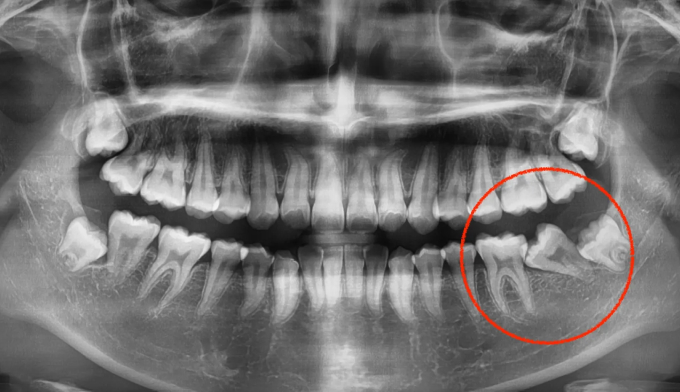

성장과정 중 어금니의 잘못된 맹출경로로 인해 쓰러지면서 나오는 경우가 종종 있습니다. 어금니가 쓰러지게 되면 해당부위에 음식이 저류되어 충치가 생기기 쉬워지며, 해당부위에 음식의 부패로 냄새와 함께 잇몸염증이 나타나기 쉽습니다. 나머지 부위에 대한 교정치료 욕구가 없다면 해당 어금니부위만 부분교정을 통해 어금니를 바로 세워줄 수 있습니다. 교정치료는 9개월 소요되었습니다.